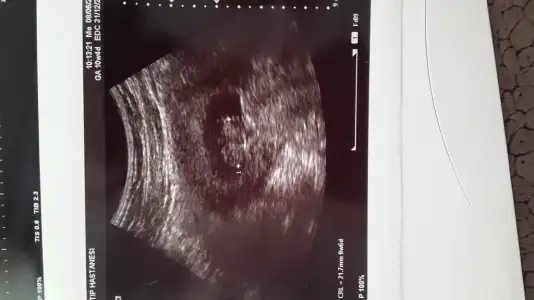

teyzeleri bakin benim melegime maşallah :KK200::nazar::KK68:

• IMG-20150608-WA0001.webp

IMG-20150608-WA0001.webp

25,8 KB · Görüntüleme: 139